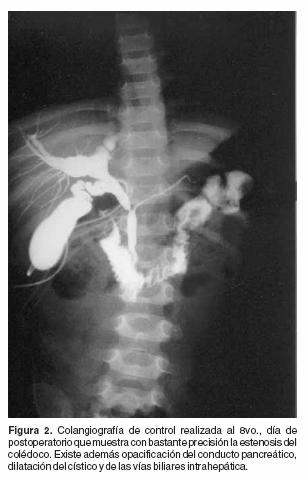

Paciente femenino de 11 meses de edad quien inició su padecimiento dos semanas antes de su ingreso con fiebre no cuantificada, evacuaciones liquidas en número de cuatro al día y vómito, motivo por el cual fue internada en un hospital general iniciándose tratamiento con alimentación endovenosa y antimicrobianos. Tres días después presentó distensión abdominal y ausencia de evacuaciones, motivo por el que fue enviada a nuestra unidad hospitalaria. A la exploración clínica se encontró sin ictericia, bien hidratada, irritable y con sonda nasogástrica instalada a través de la cual drenaba líquido biliar. El abdomen era globoso con perímetro de 52 cm, doloroso a la palpación superficial y peristalsis disminuida. La citología hemática mostró leucocitosis de 12,900, neutrófilos de 58%, linfocitos de 30% y hemoglobina de10.0 grs%. Aproximadamente 4 horas después, se efectuó laparotomía exploradora encontrándose l000 cc de líquido biliar en la cavidad peritoneal y gotas lipoidicas sobrenadantes, por lo que se exploró la vía biliar en donde se encontró una perforación de 1.2 por 0.9 cms en la unión de los conductos hepático común, cístico y colédoco. Con este hallazgo se optó por reparar la lesión y colocar en su interior de la vía biliar una sonda calibre 5F. La evolución del gasto por la sonda descendió de 100 a 5 cc cada 24 horas; en el octavo día se efectuó una colangiografía de control en la que muestra la fuga del medio de contraste (Figura 1) y dilatación de la vía biliar principal, visualización del conducto de Wirsung y en la confluencia de ambos, la estenosis producto de la colangitis crónica (Figura 2). Se inició la vía oral y fue dada de alta al 12avo día de estancia hospitalaria con citología hemática y pruebas de función hepática normales.